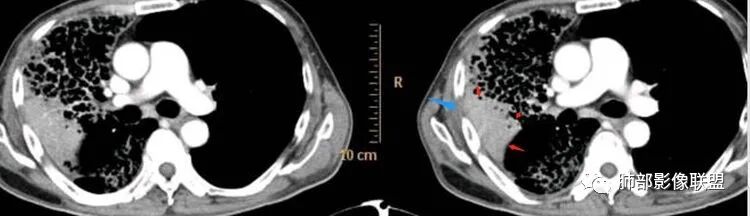

支气管在近端堵塞,或狭窄

实变近端

边缘膨隆+收缩

部分GGO边界偏清

如果要考虑鳞癌的支持点是觉得有栽赃,栽赃在粘液腺癌罕见